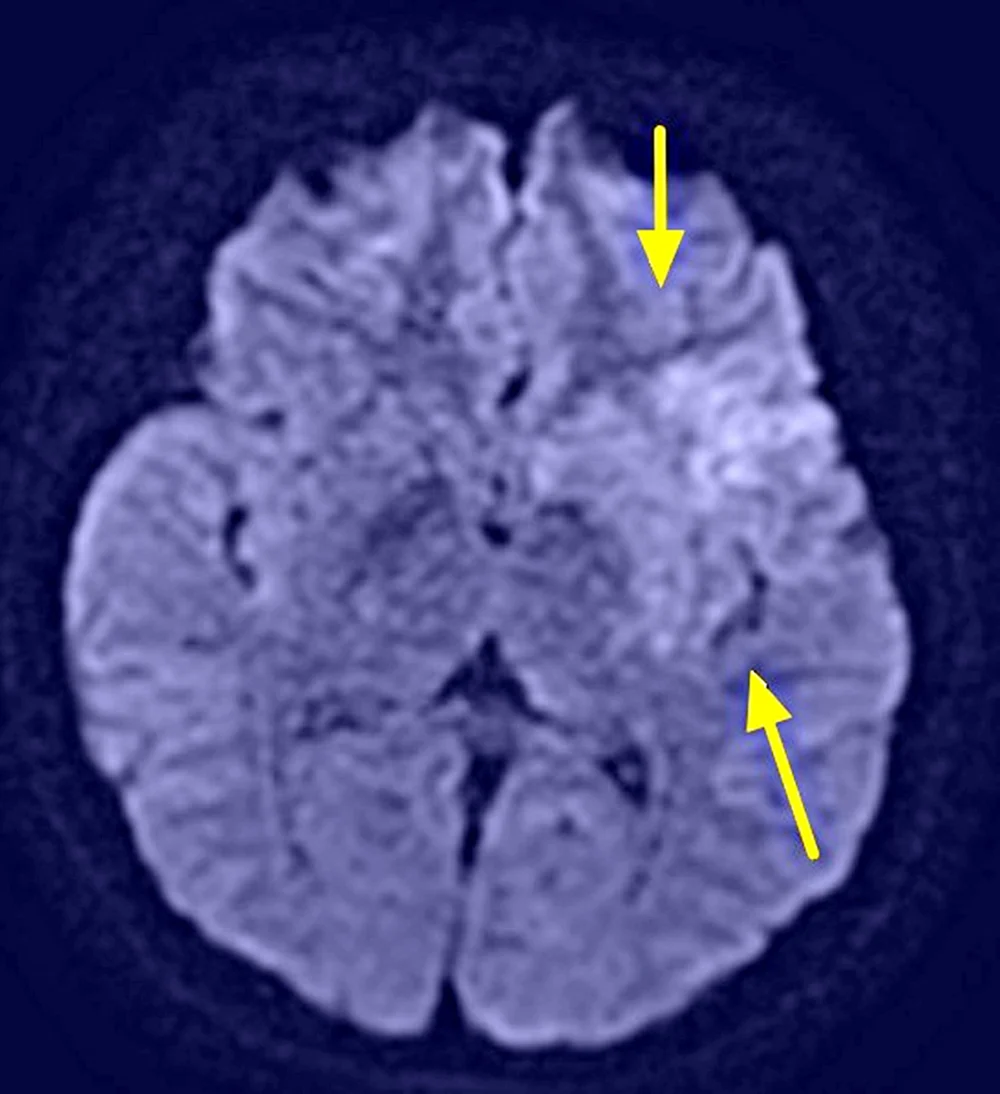

郭葉璘進一步說明左側大腦掌管語言中樞、身體右側活動能力及視覺與空間感知區域,中大腦動脈是負責供應大腦三分之二的重要血流。磁振造影中的擴散權重影像序列(DWI),能在中風發生後30分鐘內偵測腦部受損區域。檢查顯示該學生的左側中大腦動脈完全阻塞,磁振中的擴散權重影像序列也出現一塊淡淡的受損區域,這表示阻塞的危險性正快速提高中。若不即時處理,這片受損區域會持續擴大,腦部將因血栓壓迫而腫脹,同時往下壓迫腦幹,危及呼吸與心跳中樞,甚至造成生命危險。

核磁共振影像,箭頭處呈現早期缺血變化